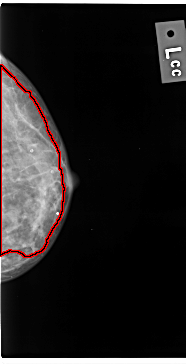

C_0039_1.LEFT_CC

LEFT_CC LINES 4728 PIXELS_PER_LINE 2408 BITS_PER_PIXEL 12 RESOLUTION 50 OVERLAY

FILE: C_0039_1.LEFT_CC.OVERLAY

TOTAL_ABNORMALITIES 1

ABNORMALITY 1

LESION_TYPE CALCIFICATION TYPE AMORPHOUS DISTRIBUTION DIFFUSELY_SCATTERED

ASSESSMENT 3

SUBTLETY 4

PATHOLOGY MALIGNANT

TOTAL_OUTLINES 1

BOUNDARY